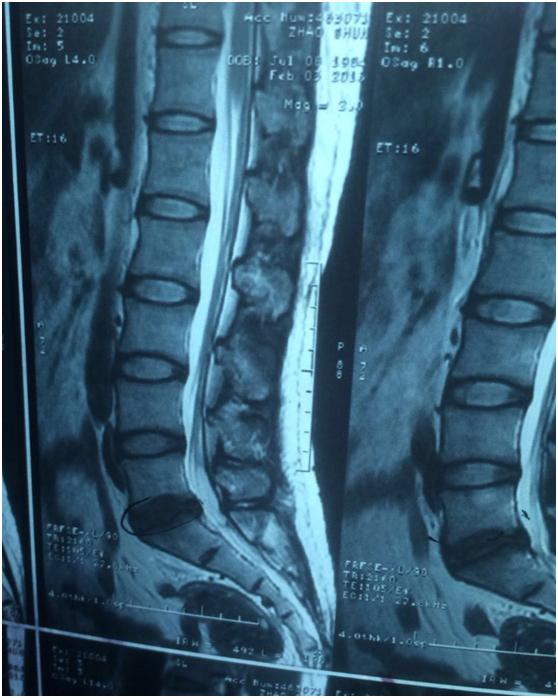

从患者的片子来看的话,虽然发的比较小,有的不太清楚,但是多数都能看清楚。从患者描述的症状来看的话,症状还是和轻度的椎间盘突出有关系。但是整个来说,压迫并不太重,而且患者症状也不是很重。